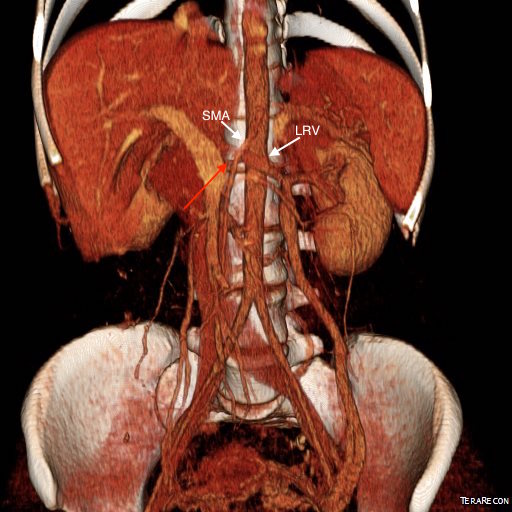

CT Venography showed the gonadal vein to be an important outflow vessel to the left renal vein with dilated proximal segment and reflux into pelvic varices.

The left renal vein transposition to the IVC is a nice operation with a good track record (ref 2). The downside is the long midline incision required with transperitoneal exposure. There is bleeding risk and postoperative complications of ileus, wound infection, and small bowel obstruction. Looking at the CTV, it seems obvious that the gonadal vein crosses over the iliac vein in the pelvis and would be a straightforward, less morbid, less invasive option. A review of the literature reveals only a single reference discussing three cases of left renal vein transposition (ref 3), and it was done with a surgical robot. I think that a laparoscopic approach would be simpler and less invasive and will consider developing this if volumes justify it. That said, the open retroperitoneal approach is very straightforward and well used exposure. Using venography to set up and then confirm the results of the transposition was helpful. I don’t think that measuring pressures and diameters and taking calipers to calculate stenoses is all that useful and in some instances a harmful method of justifying endovascular treatment of nutcracker phenomena in the absence of serious symptoms and a careful deliberate workup which includes a good history and physical, a UA, a duplex and CTV.